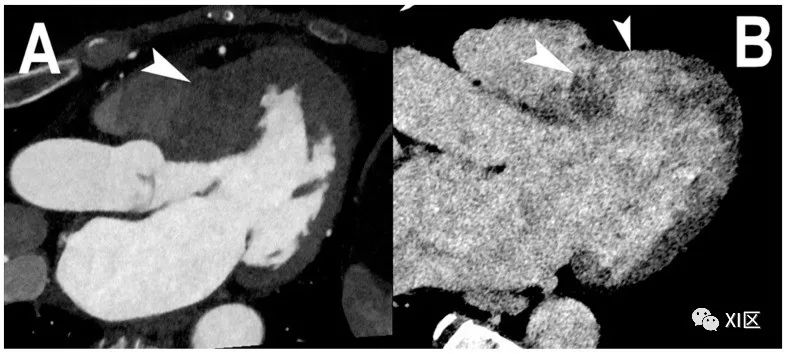

心肌延迟强化的心脏PCCT。本例(A,B)显示的是一名严重肥厚型心肌病患者的三腔投影,患者的左心室基底隔中段受到严重影响((A);箭头)。静脉注射碘基造影剂七分钟后,肥厚左心室壁的碘化CM跨壁聚集(也称为延迟增强)清晰可见((B);箭头)。这一现象与在心脏磁共振中观察到的现象相同,并在临床实践中得到证实。使用PCCT进行这种成像的特别之处在于,能谱成像与标准的心脏CT方案相关,不需要特定的方案。